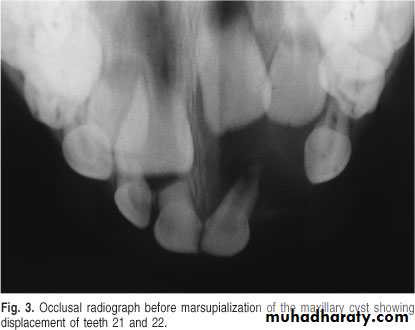

• It is located between the maxillary central incisors (which are vital). This lesion dose not exist as an entity but it represents an incisive canal cyst.• Nasopalatine Cyst

Also called nasopalatine canal cyst, incisive canal cyst, median palatine cyst , or median anterior maxillary cyst.*It is located in the midline between the upper central incisors. Note the superimposed shadow of nasal

spine causing the cyst to appear heart shaped.

The teeth are vital.

This cyst causes the roots of the central incisors to

diverge, and occasionally root resorption occur.

*Treatment by excision.